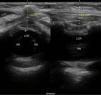

El primero (fig. 1) fue una reconstrucción de tránsito intestinal en un lactante exprematuro de 5 meses y 4kg, realizándose abordaje axial para visualizar duramadre, saco dural, raíces nerviosas y cono medular.

El segundo (fig. 2) fue una ligadura de fístula vesicorrectal en un lactante de 7 meses y 8,5kg, realizándose abordaje axial y sagital paramedial para identificar duramadre, saco dural y raíces nerviosas, y medir distancia piel-duramadre.